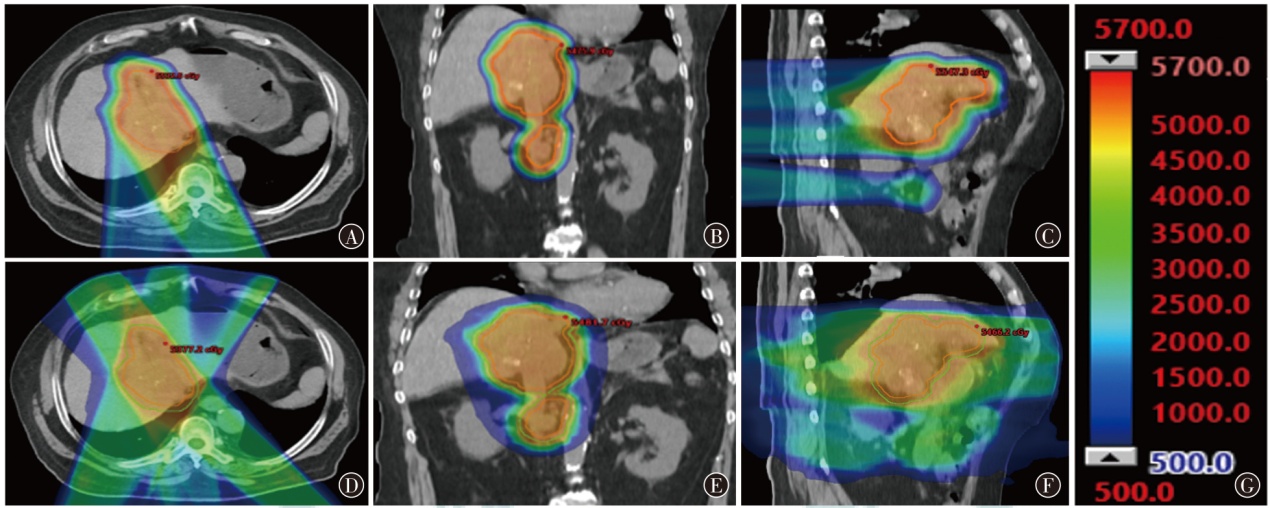

目的探讨质子调强放疗(IMPT)和光子固定野调强放疗(IMRT)应用于典型腹盆部肿瘤的剂量学特点。方法以2024年1月至6月山东省肿瘤防治研究院(山东省肿瘤医院)收治的3例腹盆部肿瘤(肝癌、宫颈癌和前列腺癌各1例)患者为研究对象,根据临床靶区和危及器官限值的要求,分别设计IMPT和IMRT两种放疗计划。评估3例患者两种放疗计划的靶区适形指数(CI)、均匀性指数(HI)和梯度指数(GI)及危及器官剂量学参数,通过评估体内10%、30%和50%处方剂量区域的体积比较患者体内额外的剂量沉积。结果3例患者IMPT计划的CI值(分别为0.61、0.62和0.43)、HI值(分别为0.053、0.075和0.020)、GI值(分别为3.45、2.63和3.80)均小于IMRT计划(CI分别为0.82、0.81和0.86;HI分别为0.060、0.120和0.080;GI分别为7.28、4.76和4.66)。与IMRT计划相比,在肝癌患者中,IMPT计划可使正常肝组织和右肾的Dmean及脊髓的Dmax分别降低37.8%、78.5%和13.2%;在宫颈癌患者中,IMPT计划可使小肠的V30,膀胱、直肠、骨髓的Dmean和脊髓的Dmax分别降低22.0%、15.7%、14.3%、12.6%和4.8%;在前列腺癌患者中,IMPT计划可使膀胱和直肠的Dmean分别降低14.9%和36.5%,但IMPT计划使左侧股骨头的Dmean及V40分别升高了35.3%和6.1%,使右侧股骨头的Dmean及V40分别升高了23.6%和10.8%。3例患者体内10%、30%和50%的处方剂量区域所占的体积,IMPT计划比IMRT计划减少了48.9%~64.8%、22.0%~47.0%、22.0%~57.7%。结论腹盆部肿瘤的IMPT和IMRT计划比较,IMPT计划在降低正常肝脏、肾脏、脊髓、小肠、直肠和膀胱等器官的剂量方面有优势;对于股骨头的剂量,IMPT计划优势并不明显;IMPT计划可显著减少患者体内额外的剂量沉积。

ObjectiveTo explore the dosimetric characteristics of intensity modulated proton therapy (IMPT) and intensity modulated radiation therapy (IMRT) for typical abdominal and pelvic tumors.MethodsThree patients with abdominal and pelvic tumors (one case each of liver cancer,cervical cancer,and prostate cancer) admitted to Shandong Cancer Hospital and Institute from January to June 2024 were selected as the research subjects. IMPT and IMRT plans were designed for each case based on clinical target volume (CTV) and organs at risk (OARs) constraints. Dosimetric parameters,including conformity index (CI),homogeneity index (HI),and gradient index (GI) for target coverage,as well as OARs dose metrics,were evaluated. The volume of additional dose deposition in the body was compared by assessing regions receiving 10%,30%,and 50% of the prescription dose.ResultsFor all three cases,IMRT plan demonstrated higher CI values (0.82,0.81,and 0.86) compared to IMPT plan (0.61,0.62,and 0.43). IMPT plan yielded lower HI values (0.053,0.075,and 0.020) than IMRT plan (0.060,0.120,and 0.080) and lower GI values (3.45,2.63,and 3.80vs. 7.28,4.76,and 4.66 for IMRT plan). In liver cancer,IMPT plan reduced the Dmeanof normal liver tissues and right kidney by 37.8% and 78.5%,respectively,and decreased the Dmaxof spinal cord by 13.2%. For cervical cancer,IMPT plan reduced the V30of the small bowel by 22.0%,Dmeanof the bladder,rectum and bone marrow by 15.7%,14.3% and 12.6%,and spinal cord Dmaxby 4.8%. In prostate cancer,IMPT plan lowered bladder and rectal Dmeanby 14.9% and 36.5%,respectively,but resulted in an increase of 35.3% and 6.1% in the Dmeanand V40of the left femoral head,respectively,and an increase of 23.6% and 10.8% in the Dmeanand V40of the right femoral head,respectively. IMPT plan reduced the volumes receiving 10%,30%,and 50% of the prescription dose by 48.9%-64.8%,22.0%-47.0%,and 22.0%-57.7%,respectively,compared to IMRT plan.ConclusionsComparison between IMPT and IMRT plans for abdominopelvic tumors: IMPT plan offers advantages in reducing doses to normal organs such as the liver,kidneys,spinal cord,small intestine,rectum,and bladder. However,its advantage is less pronounced regarding the dose to the femoral heads. IMPT plan notably minimizes additional dose deposition within the body.